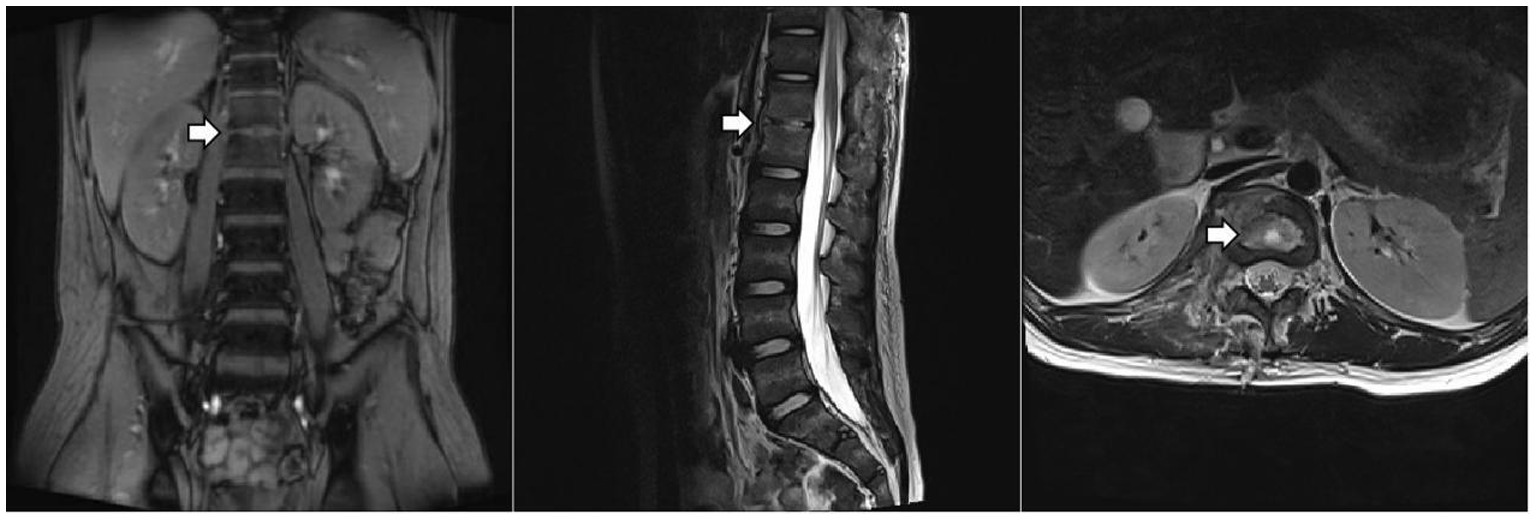

The patient underwent a series of tests to identify the cause of his illness, all of which were negative. These included urine and blood cultures, Epstein–Barr virus (EBV) DNA and antibody tests, serum 1,3-β-D-glucan and galactomannan tests, tuberculin skin test (TST), interferon-gamma release assay (IGRA), cryptococcus neoformans antigen test, serologic markers for hepatitis B, HIV antibody test, Treponema Pallidum antibody test, blood metagenomic next-generation sequencing (mNGS), and bone marrow culture. His serum immunoglobulin levels were normal, as were the counts and percentages of B, NK, and T lymphocytes. Computed tomography of the chest and abdomen showed pulmonary nodules, liver and spleen enlargement, intervertebral space narrowing from T12 to L1 with nodules, and local compression of the adjacent vertebral body. Thoracolumbar magnetic resonance imaging (MRI) (Figure 1) showed bone marrow edema of T12-L1, local bone destruction of T12 and L1, narrowing of the corresponding intervertebral space, abnormal signals in the intervertebral disc, paraspinal soft tissue swelling, and a right psoas muscle abscess.

Figure 1. Thoracolumbar MRI. The arrow indicates localized bone destruction of the T12 and L1 vertebral bodies, narrowing of the intervertebral spaces, and abnormal signals within the intervertebral discs.